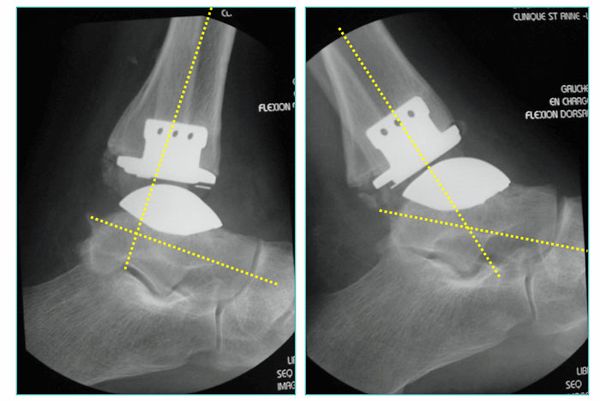

Die rekonstruktive Versorgung mit einer Sprunggelenksendoprothese ermöglicht dem Patienten im Vergleich zur Fusion eine wesentlich schnellere Mobilisierung mit Erhalt der Abrollvorgänge. 6 Wochen nach dem operativen Eingriff ist in der Regel das Laufen ohne Gips mit voller Belastung erlaubt. Dennoch eignet sich nicht jedes Gelenk für eine Endoprothese. In Fällen von hochgradigen Bandinstabilitäten oder erheblichen Knochenverformungen ist weiterhin die Fusion die Therapie der Wahl.

Abb.6: Zementfreie Dreikomponenten Sprunggelenkendoprothese. Bewegungsumfang nach Einbau der Endoprothese, gemessen im Röntgenbild

Das von uns verwendete Implantat ist charakterisiert als zementfreie, duale Titan-Hydroxylapatit beschichtete, nach dem mobile-bearing Prinzip konzipierte, totale Endoprothese des oberen Sprunggelenkes, bestehend aus drei Komponenten mit anatomischen Design.